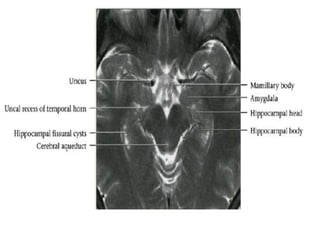

-Uncus	forms	medial	border	of	temporal	lobe,	merges	posteriorly	with	parahippocampal

gyrus.

•  The	uncal	recess	of	the	temporal	horn	of	the	lateral

ventricle	turns	medially,	separaHng	the	amygdala	(A)

from	the	hippocampal	head	(H).

(A)	Amygdala	(large	arrow),	uncus	(short	arrow),	free	margin	of

tentorium	cerebelli	(thin	arrow).

Coronal	T2	MR	images(a,b,c)	from	anterior	to	posterior,

demonstraHng	the	main	limbic	structures	of	the	mesial

temporal	lobe

(B)	Hippocampal	head	(large	arrow),	uncal	recess	of	temporal	horn	separaHng

posterior	aspect	of	amygdala	superiorly	from	hippocampal	head	inferiorly.

*Hippocampal	head	is	recognized	by	digitaHons	on	its	superior	surface.

(C)	Body	of	hippocampus	(large	arrow),	parahippocampal	gyrus	(long

arrow),	collateral	sulcus	(short	arrow).

*Collateral	sulcus	separates	parahippocampal	gyrus	from

occipitotemporal	(fusiform)	gyrus.